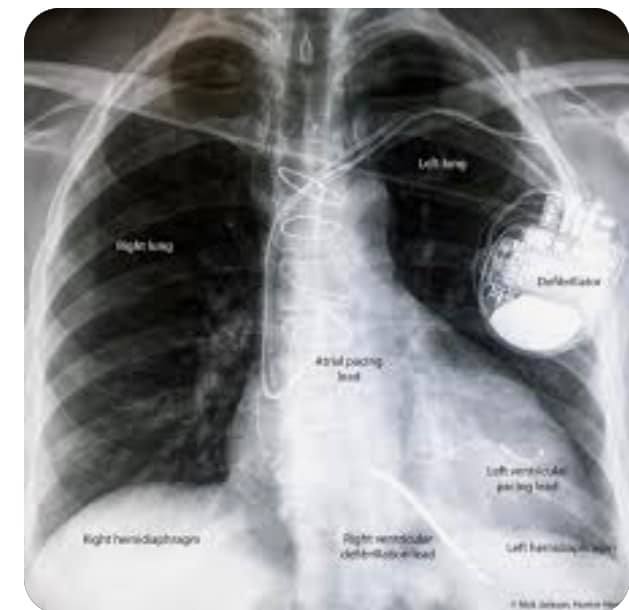

وقال جمال شعبان "رسم القلب بيوضح لسداد في حزمة الكهربا اليسري وكفاءة البطين الأيسر أقل من ٣٠%.. الحالات دي بنزرع فيها الجهاز الكهربي الثلاثي دا CRTD، الجهاز دا بإذن الله معجزة، زي مانتم شايفين في الصورة بطارية طالع منها ٣ كابلات دقيقة"

وتابع شعبان "زراعة الكابلات جوًا القلب لازم تبقي في نقط معينة وبتحتاج دقة رهيبة ومهارة عالية وتوفيق كبير من ربنا، واحد في الأذين الأيمن واحد في البطين الأيمن اللي طرفه عريض، ودا الكابل اللي بينقل الصدمة الكهربية واحد في الوريد الجيبي لتحفيز البطين الأيسر"